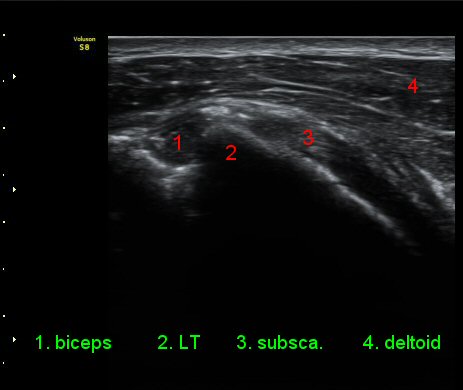

ÀÌµÎ¹Ú±Ù°Ç È¾´Ü¸é°Ë»ç¿¡¼­ °ÇÁÖÀ§¿¡ ¼Ò·®ÀÇ ¼ö¾×Àú·ù¿Í Á¡¾×³¶³» ¾×Àú·ù°¡ °üÂûµÈ´Ù(»çÁø 1, 2).

ŽÃÊÀÚ¸¦ ¾à°£ ´Ù¸®ÂÊ, ³»ÃøÀ¸·Î À̵¿ÇÏ´Ï °ß°©ÇÏ±Ù°Ç Ç¥Ãþ¿¡ ¸¹Àº ¾çÀÇ ¼ö¾×Àú·ù°¡ °üÂûµÈ´Ù(»çÁø 3).

ÆÈÀ» ¿ÜȸÀüÇÏ´Ï °ß°©ÇÏ±Ù°Ç Ç¥ÃþÀÇ ¼ö¾×Àú·ù°¡ ´õ¿í È®½ÇÇÏ°Ô °üÂûµµ´Ï´Ù(»çÁø 4).